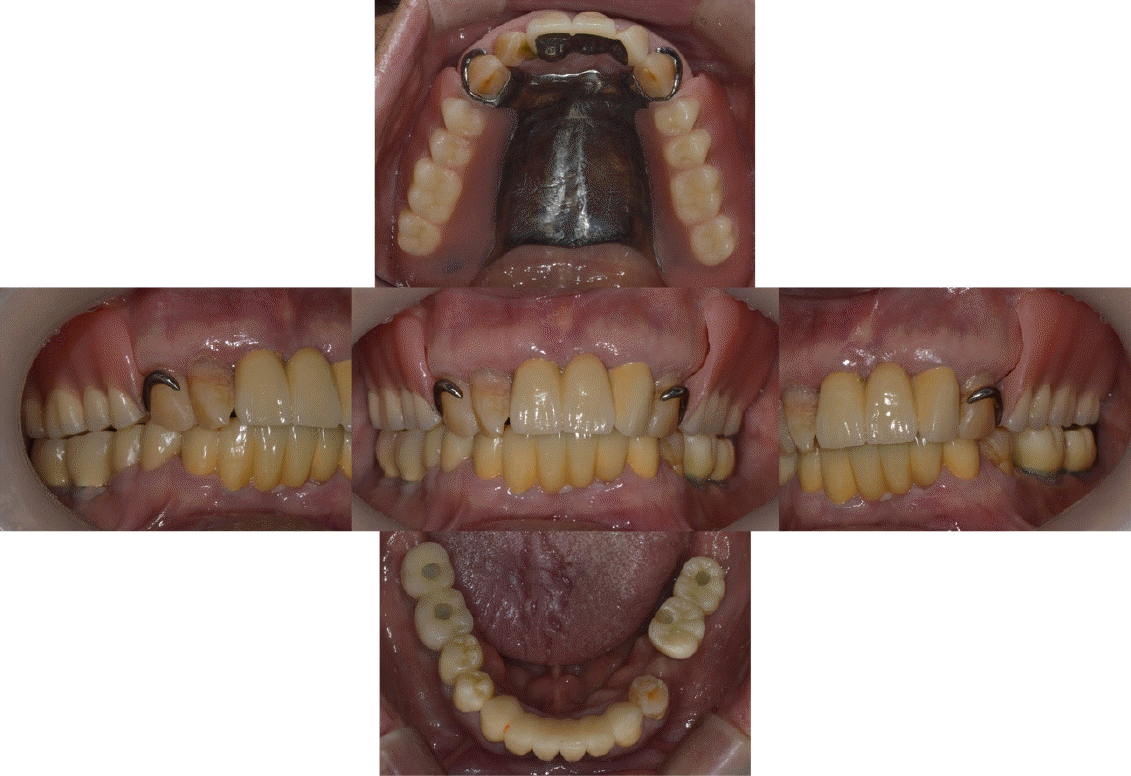

본 증례의 환자는 76세의 여성으로 상악 6전치만 잔존한 상태로 상악 가철성 국소의치의 제작을 위해 내원하였다. 상악은 6전치 중 상악 우측 견치와 좌측 견치의 상태는 동요도 및 파절 상태 없이 양호하였고, 상악 우측 측절치는 총생 상태였으며, 상악 우측 중절치와 상악 좌측 측절치를 이용해 3본 고정성 가공의치 형태로 상악 좌측 중절치의 수복이 되어 있는 상태였고, 상악 잔존 치조제의 상태는 중등도의 흡수 상태가 관찰되었다. 하악은 하악 좌측 제 2소구치는 잔존 치근 상태였다(Fig. 1). 상악의 경우엔 임시의치를 사용중이었고, 잔존 치근 상태인 하악 좌측 제 2소구치는 발거를 진행하였다. 전신병력으로는 B형 간염, 신장 투석, 파킨슨, 당뇨, 고혈압 및 협심증으로 다양한 약을 복용중이었고 비용 및 전신병력의 이유로 임플란트와 같은 수술적인 치료방법의 치료는 어려운 상태였다.상악은 양측 구치부의 결손이 있는 Kennedy Class I 으로 분류하고, 후방 결손부의 수복을 위해서 상악 가철성 국소의치의 제작을 진행하기로 결정하였다. 상악 가철성 국소의치의 디자인은 양측 상악 견치에 후방연장 국소의치의 유지를 위해 설면 레스트와 원심 유도면, 조직 언더컷으로 인해 RPA 클라스프를 설계하였고, 잔존 치아의 개수가 적어 주연결장치는 구개부를 대부분 피개하는 구개판형 연결장치를 설계하였다. 간접 유지의 역할을 위해 추가적인 설면 레스트의 부여를 고려하였으나 양측 측절치에 설면 레스트의 형성은 상악 우측 측절치의 총생 및 상악 좌측 측절치의 기존 보철 수복물로 인해 한계가 있었다(Fig. 2). 의치의 무게로 인한 탈락을 최대한 보완해보고자 금속 구조물의 제작을 코발트-크롬 합금보다는 보다 가벼운 특징을 가진 티타늄 합금(Ti-6Al-4V)을 이용하여 제작하기로 결정하였고, 7년 이내 요양급여를 통한 보험의치 적용을 받은 기록이 있어 비보험 진료로 진행하기로 하였다.해당 수복의 진행을 위해 양측 견치에 설면 레스트 시트를 구강 내 직접 형성 하였고 삽입 철거로를 고려하여 원심면의 치질 성형을 시행하였다(Fig. 2). 이후 개인 트레이를 제작 후 부가중합형 실리콘(Selection-K V.P.S, Shinhung Co., Seoul, Korea)를 이용해 기능인상채득을 시행하였다(Fig. 3). 이후 주모형을 제작하였고 제작된 주모형을 모델 스캐너(DOF Freedom HD, DOF Inc., Seoul, Korea)를 이용해 스캔하여 디지털 데이터를 형성하였다(Fig. 4). 이후 디지털 데이터를 이용하여 CAD 프로그램(3Shape dental system, 3Shape Inc., Copenhagen, Denmark)를 이용하여 금속 구조물을 디자인하였다(Fig. 5). 이후 해당 디자인된 금속 구조물을 선택적 레이저 용융 방식(SLM)의 3D 프린터(David 1.0, Merain Co., Incheon, Korea)를 이용하여 티타늄 합금(Ti-6Al-4V)으로 금속 구조물을 제작하였다. 또한 티타늄 합금과의 무게 비교를 코발트-크롬 재질의 금속 구조물도 티타늄 합금(Ti-6Al-4V)의 금속 구조물 제작에 사용한 동일한 CAD 파일을 이용하여 3D 프린팅을 통해 제작하였다.제작한 티타늄 합금(Ti-6Al-4V)과 코발트-크롬 합금의 금속 구조물의 후처리를 완료 후 주모형에 적합도 확인 및 무게 측정을 시행하였으며, 티타늄 합금(Ti-6Al-4V) 금속 구조물의 무게는 5.6g 이었고, 코발트-크롬 합금의 무게는 9.5g으로 티타늄 합금(Ti-6Al-4V)의 무게가 코발트-크롬 합금보다 41% 정도 더 가벼운 무게를 나타냈다(Fig. 6).제작된 티타늄 합금(Ti-6Al-4V) 금속 구조물의 적합을 환자 구강내에서 확인하였고, 이후 기록상을 제작하여 악간관계 기록을 채득 후 교합기에 부착하여 치아배열을 시행하였으며, 균일하게 중심교합 시 균일한 교합접촉을 이루는지 확인하였다(Fig. 7).

Figure 6.

The titanium alloy (Ti-6Al-4V) framework (A) weight 5.6 grams, while the Co-Cr alloy framework (B) weights 9.5 grams

Figure 7.

Maxillomandibular relationship record using a recording base (A) and arrangement of artificial teeth (B)